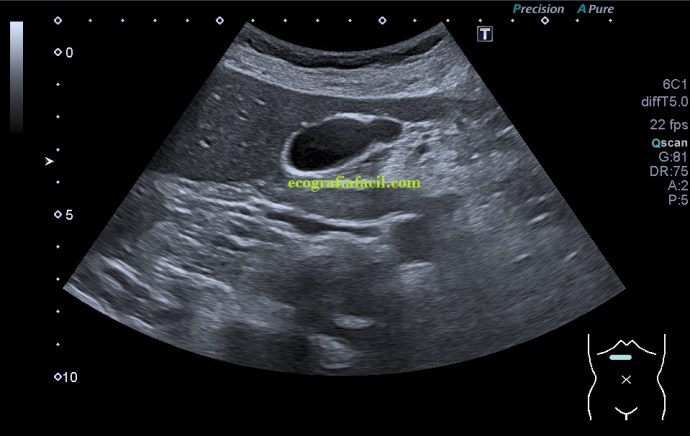

En la imagen 1 la ecoestructura era absolutamente normal, sacular, alargada y anecoica en longitudinal, pero en la imagen 2 se presenta una estructura en una forma anómala, variante de la normalidad, que en ecografía se denomina «vesícula en gorro frigio», su aspecto recuerda a este tipo de gorros de forma cónica con punta curvada que históricamente han acompañado a la humanidad en multitud de situaciones, te dejo el enlace (cultura general) por si te apetece leer un poco…es curioso.

Sumado a esta peculiar presentación encontramos que en la curvatura sacular, en el fundus de la vesícula, «en la punta» que se objetiva en la imagen 2, percibí como si la pared en ese punto estuviera ligeramente engrosada, pero no terminaba de verlo como yo quería así que cambié la sonda, de cónvex a lineal, adapté los parámetros o ajustes ecográficos y la imagen de la pantalla era preciosa, se veía la imagen sacular, muy definida, gracias a la alta frecuencia de la sonda lineal, con una definición muy importante que me permitió documentar como en la pared de la vesícula, imagen 4, existía engrosamiento mural. Se usa el cónvex virtual o trapezoidal, como ajuste que permite ampliar el scan range de la pantalla con el uso de la sonda lineal.